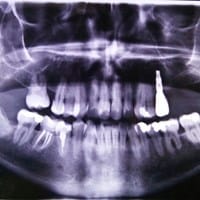

Yo haría radiografía, tratamiento de conducto, y ortodoncia..